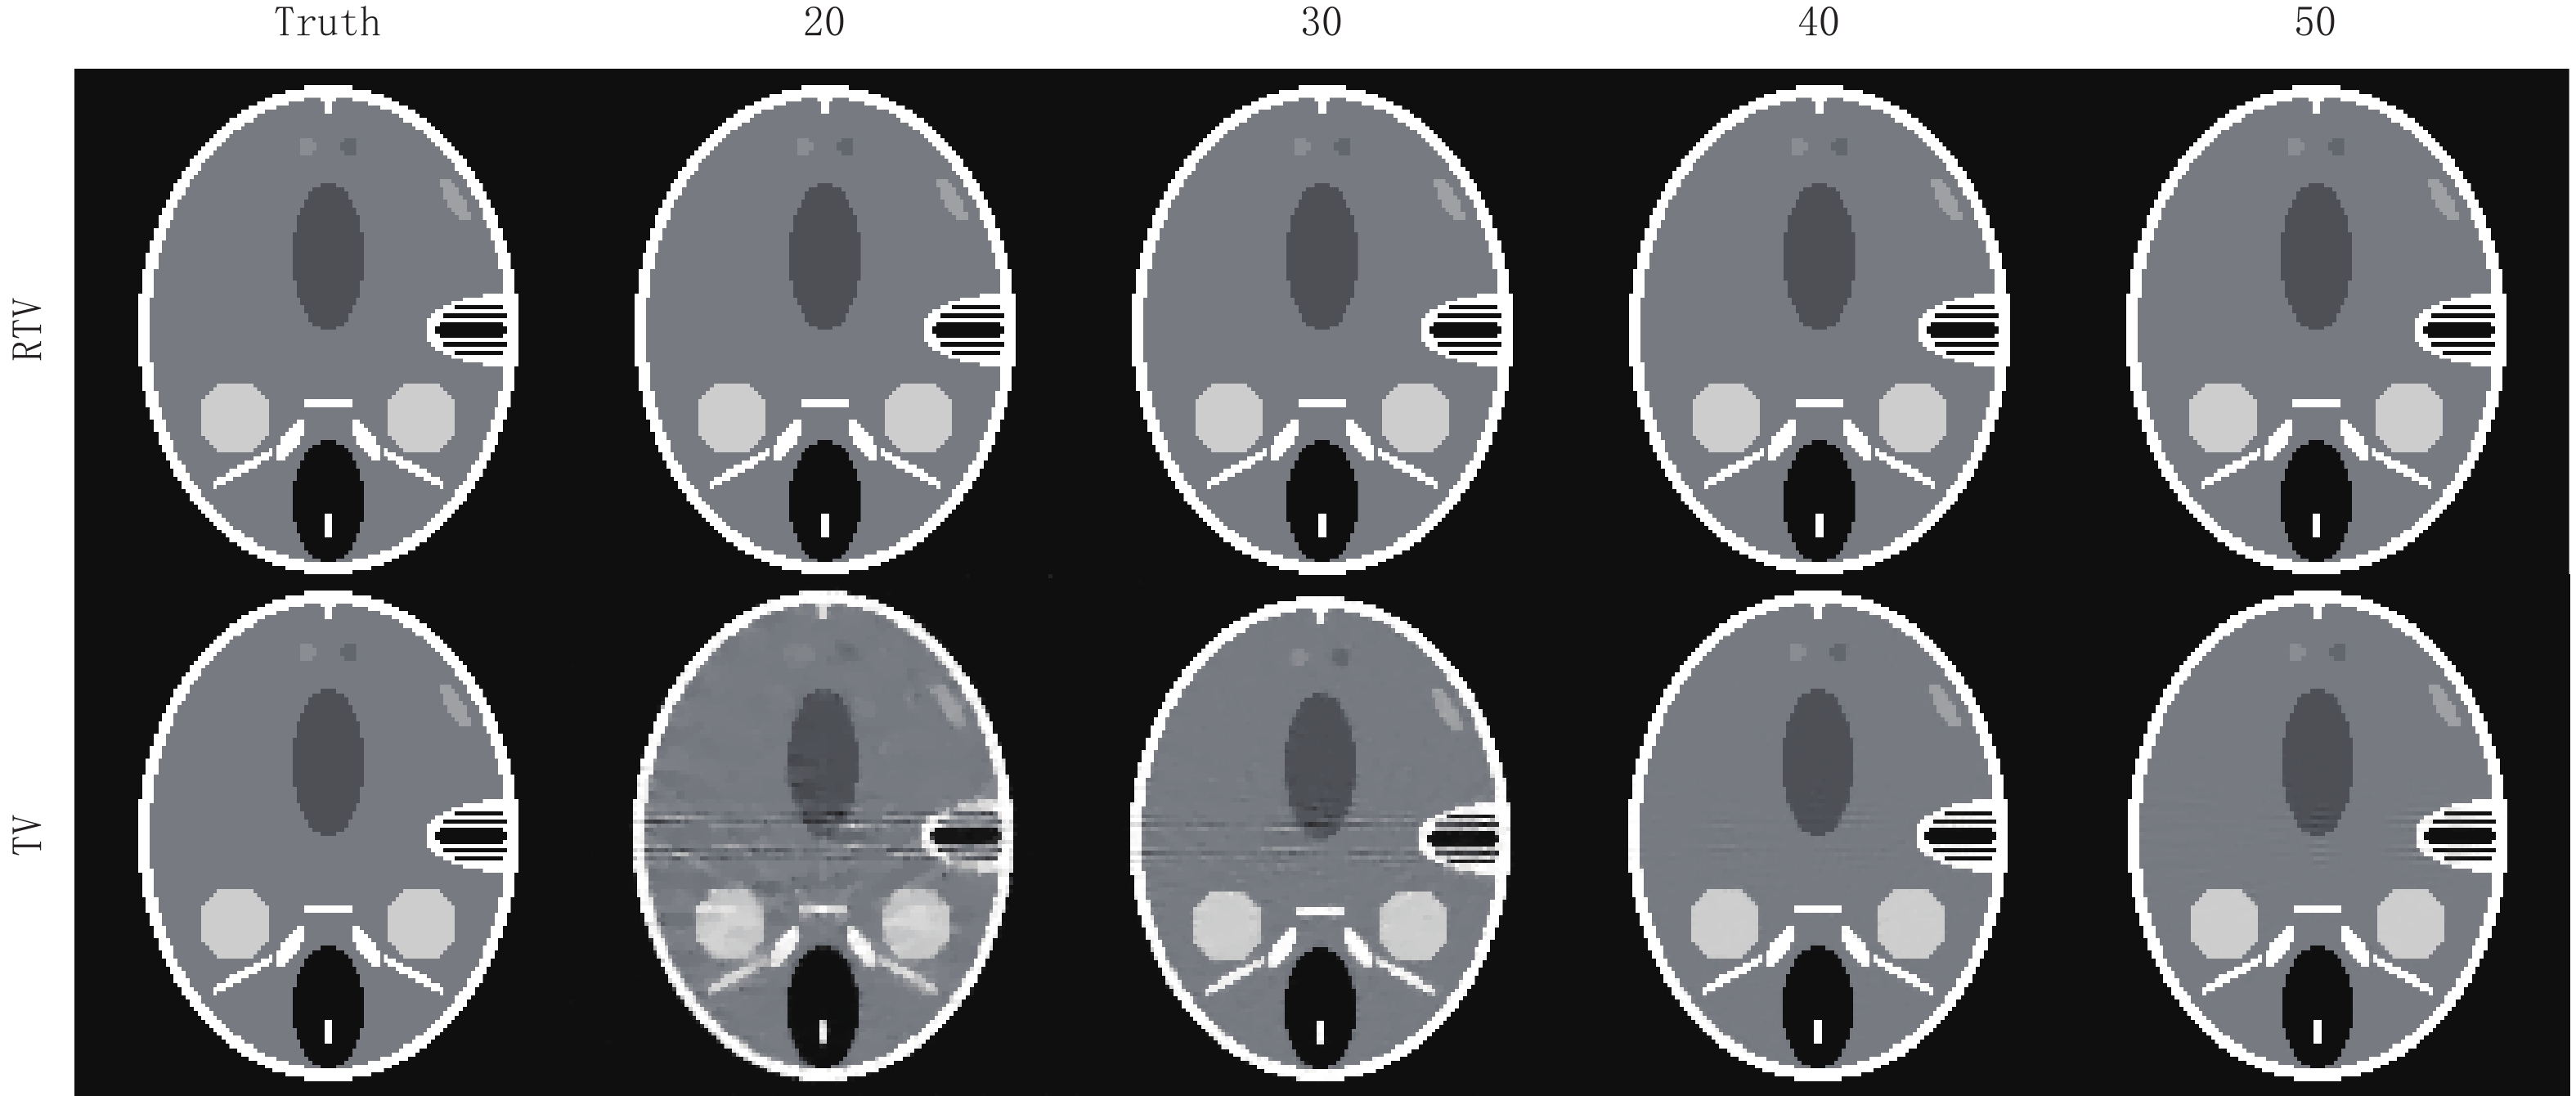

3.2 算法稀疏重建能力的评估与正则项各参数的选取

为了评估RTV算法的稀疏重建能力,本节实验分别使用RTV算法和TV算法对FORBILD、Shepp-Logan和真实CT图像模体在20,30,40,50个投影角度下进行模拟实验。这些模体的大小都是128

$ \times $ 128。在实验分析中,使用均方根误差(RMSE)和结构相似性(structural similarity,SSIM)作为图像重建质量的度量。在文献[2]对ASD-POCS算法的阐述中,数据容差

图6中的(a)图显示了FORBILD模体在20个投影角度下使用RTV和TV最小化重建算法的RMSE趋势曲线的比较,显然,RTV最小化重建算法经过500次迭代达到收敛点后拥有更高的重建精度,其最终的收敛精度是30×10-5。而TV算法最终的收敛精度只有5130×10-5。

表1比较了使用RTV算法化和TV算法在20到50个投影角度下重建FORBILD模体的均方根误差(RMSE)和结构相似性(SSIM)的比较,可见RTV算法的重建图像比TV算法的重建图像有更高的重建精度和结构相似性。

表 1 RTV算法和TV算法重建FORBILD模体的RMSE和SSIM比较Table 1. RMSE and SSIM comparison of RTV and TV algorithms for FORBILD phantom reconstruction项目 算法 投影个数 20 30 40 50 RMSE RTV 30.0×10-5 9.96×10-5 7.11×10-5 5.60×10-5 TV 5130×10-5 2530×10-5 620×10-5 590×10-5 SSIM RTV 0.9587 0.9792 0.9972 0.9992 TV 0.9293 0.9583 0.9943 0.9986 图7显示了两种算法关于FORBILD模体的重建结果。在20个投影角度下,TV算法重建结果有明显的伪影和噪点,并且有多处图像细节也被平滑掉。从20个到50个投影角度,其重建图像的精度虽然不断升高,不过一直到50个投影角度时,其重建图像与原图相比还是有些明显的伪影。而同样在20个投影角度的情况下,RTV最小化算法重建结果用肉眼几乎看不出与原图的区别。随着投影角度的增加,其重建结果与原图相比还是一致的。显然RTV算法的重建效果更好一点。